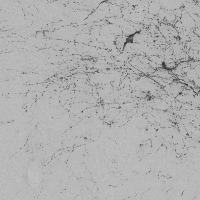

The provided information seems to be insufficient to provide detailed use-cases. The model name, "dopamine_th" implies a possible connection to neurobiology, specifically, to dopamine neurotransmitters. Yet, the "th classes including th" part is unclear, as "th" is not a known term in either computer vision, biology, or bioinformatics domain. It might be a reference to certain classes in your data set, but without further context or clarification, it's challenging to provide accurate use cases. The image of a grey background also doesn't provide significant context. Could you please provide further details concerning this "th" term and more context related to the computer vision model?